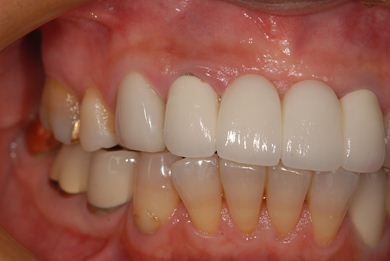

治療後

• 治療後